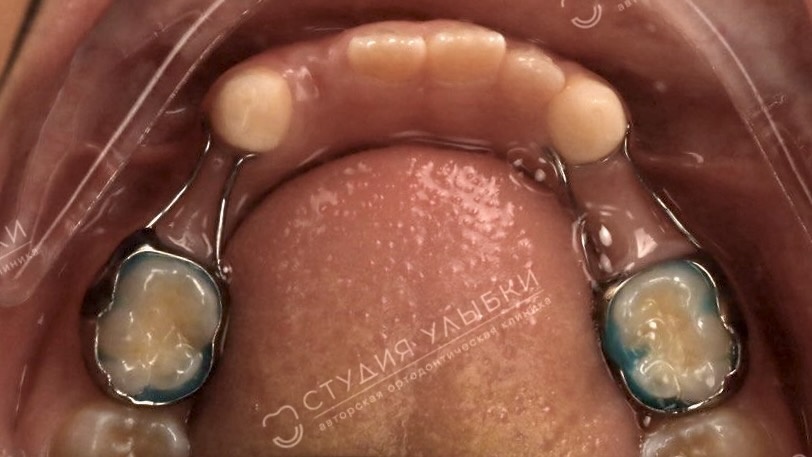

Аппарат ХААС — расширитель верхней челюсти